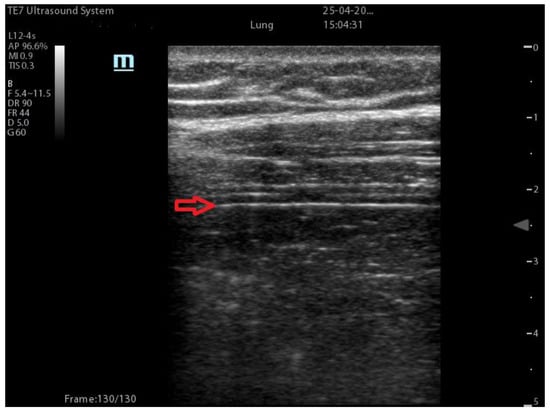

| Coalescent Lung score c-LUS [10,11] | Score 0: presence of A-lines, maximum 2 B-lines Score 1: ≥3 well-spaced B-lines Score 2: coalescent B-lines Score 3: tissue-like pattern | ![]() 12 AREAS |